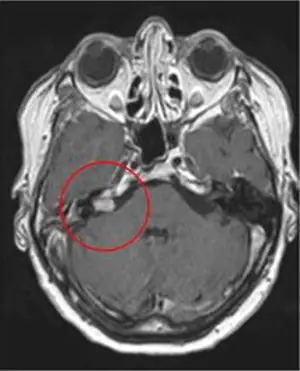

На МРТ-изображении акустическая невринома, в правой части мозжечка

Результат после одного сеанса лечения Киберножом спустя 2.5 года. Виден типичный рубец в области внутреннего слухового прохода. Доброкачественная опухоль была успешно вылечена